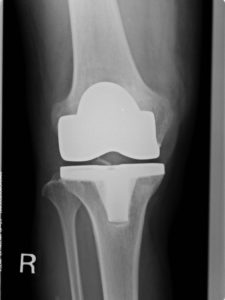

放射線科